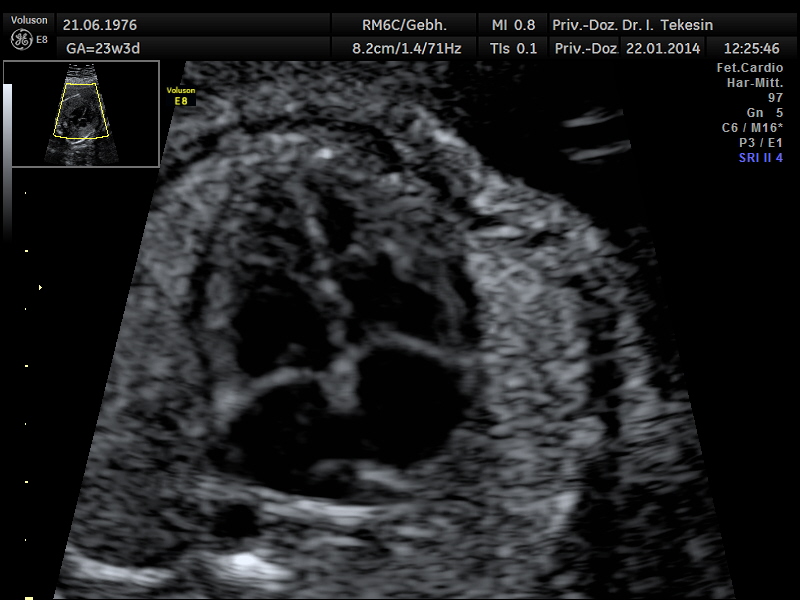

Normaler Vierkammer-Blick mit Farbe

Normales Herz in der 22. Woche